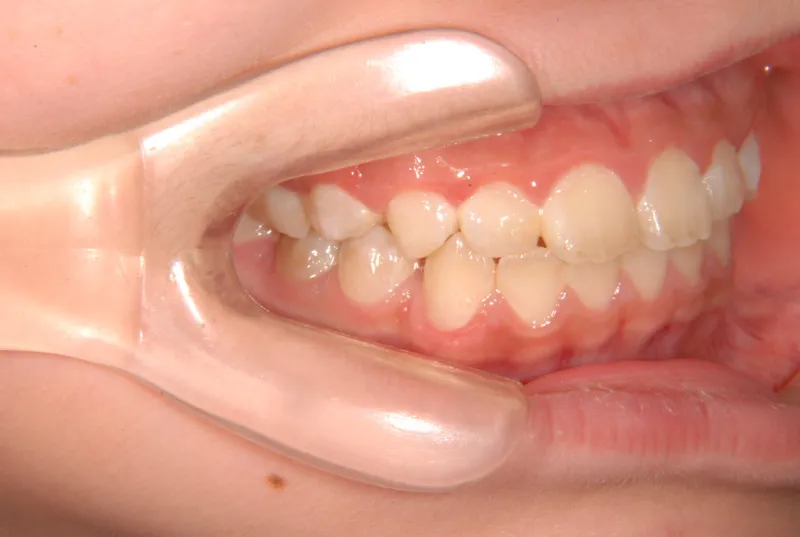

治療回数21回、2年7ヶ月の治療期間で矯正治療を終了しました。

主訴が改善され、ご満足頂きました。

治療終了後